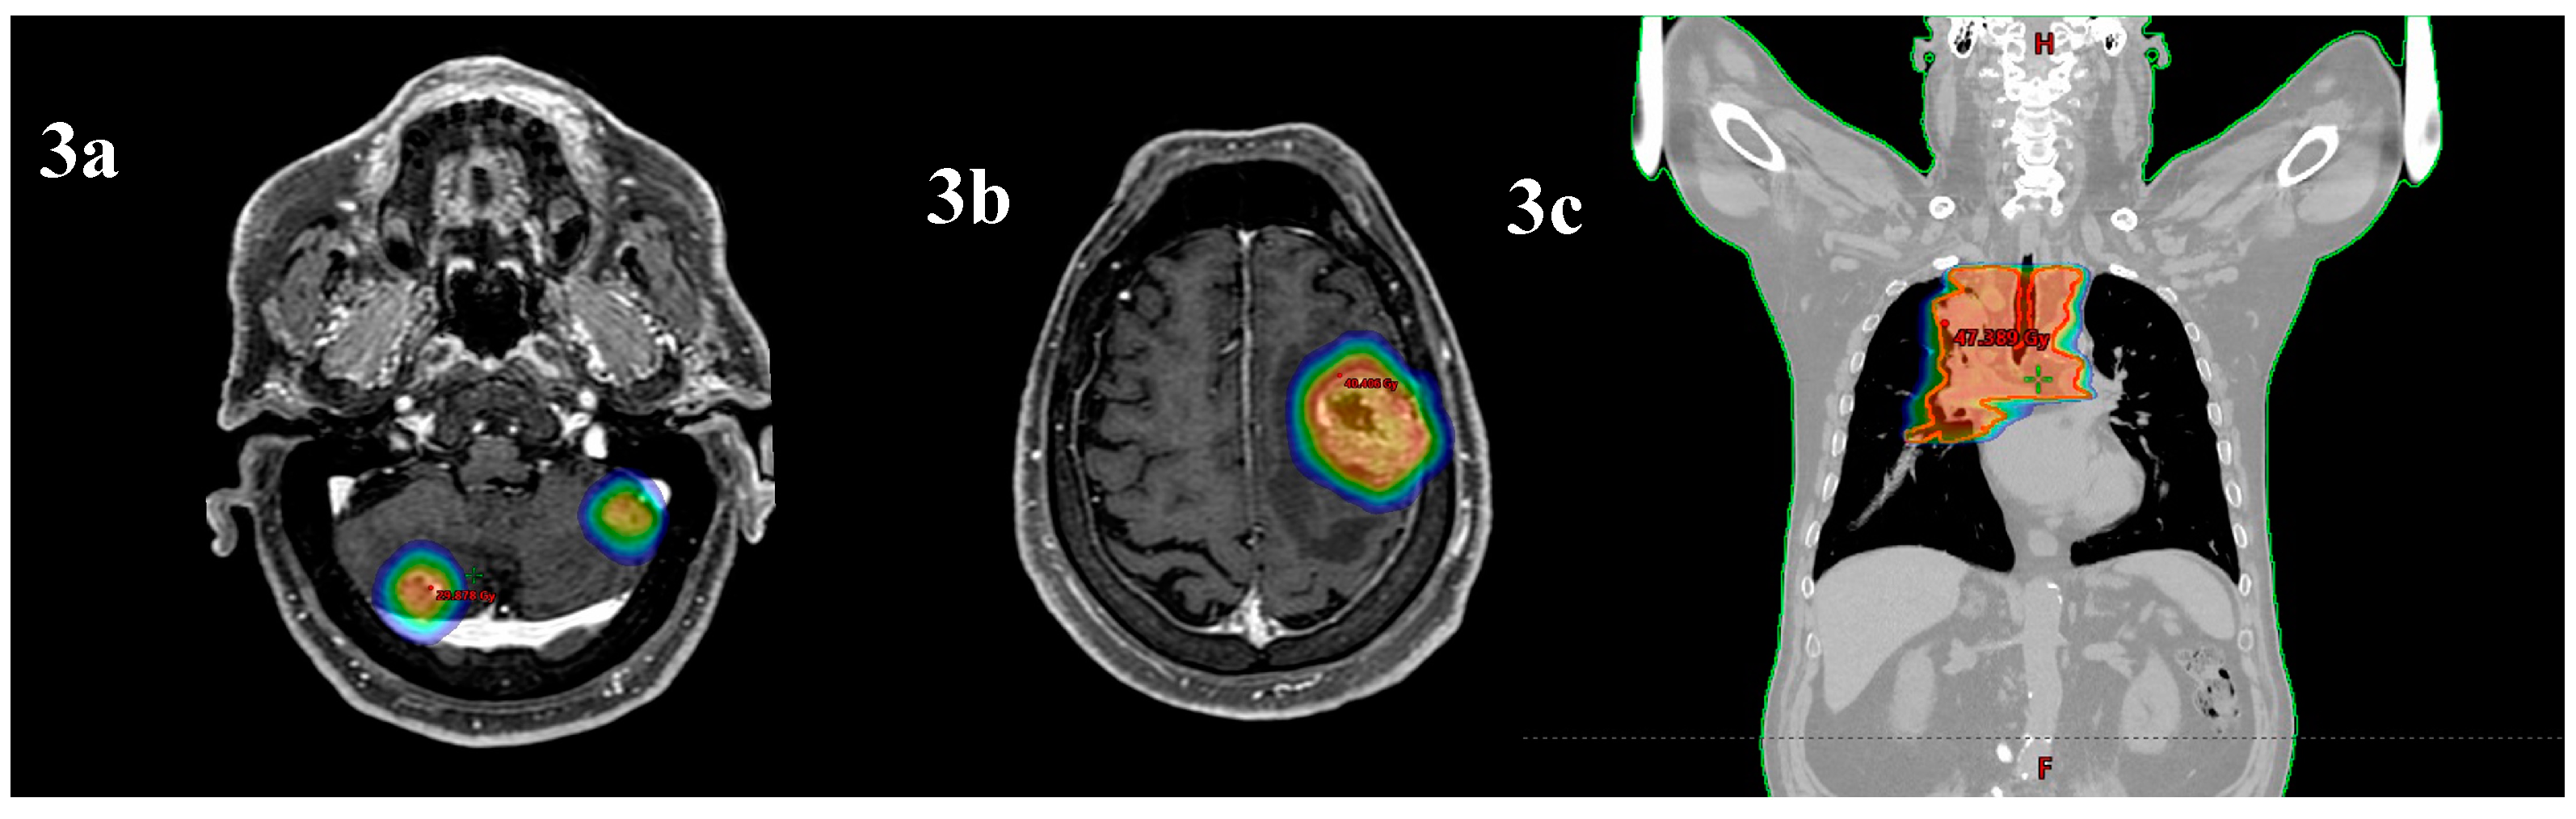

ICI was discontinued, as agreed with the patient, considering his adverse reactions. The patient developed hypothyroidism (TSH 64 UI/ml, range 0.27-4.2) with heart failure treated with levothyroxine, Grade 4 dermatitis from psoriasis, and pruritus unresponsive to antihistamines, which was managed with glucocorticoids. The patient resolves the side effects 3-4 months after the Atezolizumab interruption. Moreover, patients reported chronic cystitis with hematuria and, in July 2024, underwent a cystoscopy and a biopsy was performed. The result was bladder fragments with massive ulcer-necrotic phenomena and chronic granulomatous, giant cell and histiocytic inflammatory process (CKAE1/AE3 negative, Figure 4).

Figure 4. Bladder biopsy. Legend: biopsy evidence of inflammatory process.